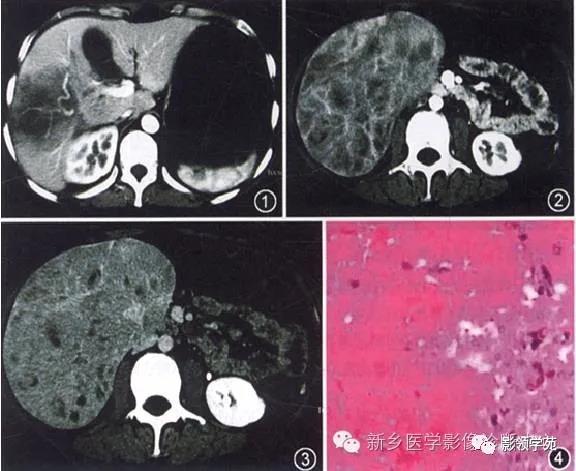

9、血管肉瘤

血管肉瘤又称恶性血管内皮细胞瘤,是一种肝血窦壁细胞异常增生所形成的原发性恶性肿瘤,肉眼观肿瘤为灰棕色结节性肿块,可多发,肿瘤易发生出血。

发病年龄50~60岁,男性多见。本病可为先天性血管内皮恶变,也可为后天发生。有报告发现肿瘤与酒精性肝硬化及接触放射性物质有关。肝血管肉瘤预后差,早期常发生肺、骨转移。

CT诊断要点

平时呈低密度肿块灶,境界多较清楚。增强扫描早期病变示边缘强化,随着时间的延伸,强化逐渐向中心扩张,仍为低密度。表现与海绵状血管瘤 相似,但与之相比,肿瘤染色、增强更为显著,内部结构形态更为复杂,并可为多发性病变,弥漫性侵及全肝。且有恶性征象。